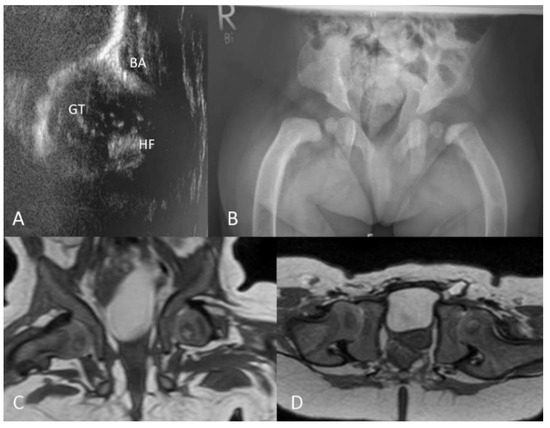

3.2.4. Ultrasound

3.2.5. MRI